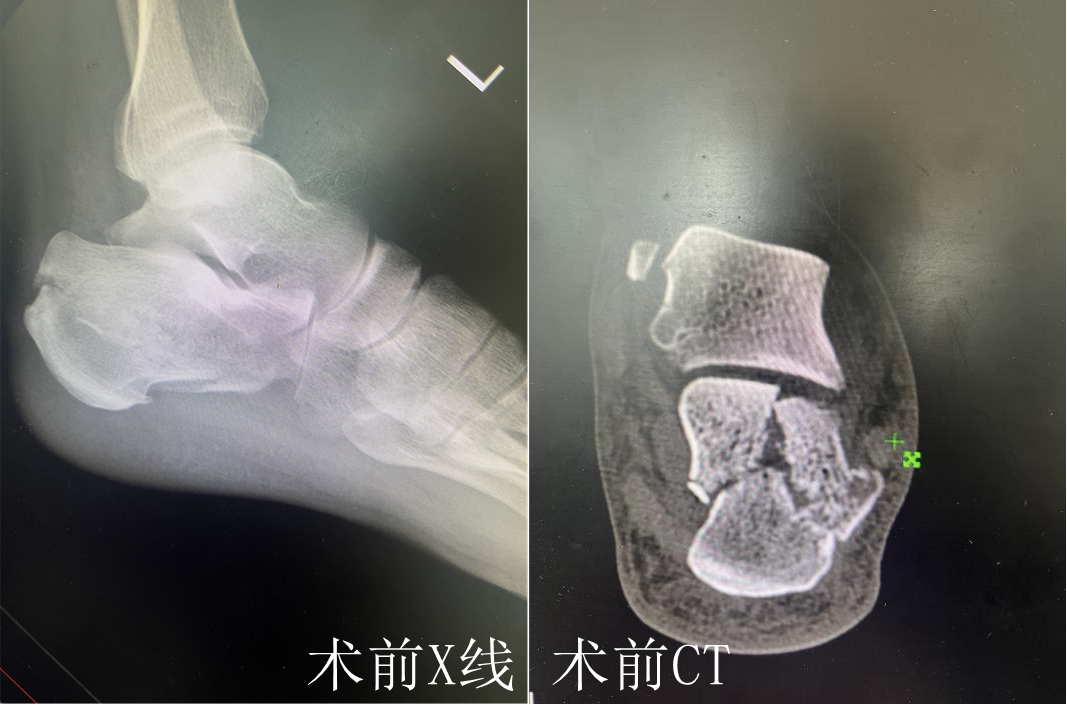

这名患者姓张,因外伤致左跟骨骨折,经人介绍来到九江市骨科医院骨伤一科就诊,骨科中心主任兼骨伤一科主任龙玲带领团队讨论,综合评估患者情况后,与患者及家属充分沟通并取得同意后,为其实施跟骨交锁髓内钉内固定术。

龙玲介绍说,跟骨是人体最大的跗骨,承担着身体绝大部分重量,其骨折通常由高处坠落、交通事故等高能量损伤导致,治疗极为困难。传统大面积的手术创伤可能导致皮瓣坏死、伤口感染、内置物外露等严重并发症,患者术后往往需要很长的恢复期,甚至可能因疼痛和关节僵硬而影响远期功能。

与传统方案不同,跟骨交锁髓内钉技术代表了一种全新的“内固定”理念。该技术仅需在跟骨结节下方(脚后跟处)切开一个约1厘米的小切口,将一枚特制的髓内钉主钉置入跟骨内部的骨髓腔中。通过主钉远端的多向交锁螺钉,可以牢牢“抓住”碎裂的跟骨前部和关节面骨块;近端的交锁螺钉则能提供强大的稳定性,有效恢复跟骨的高度、宽度和关节面的平整,整个过程对周围软组织的损伤降到了最低。